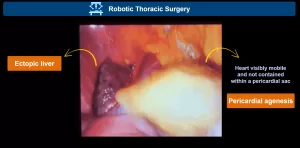

Congenital Absence of the Left Pericardium

Axial chest MRI of a healthy control (A) demonstrates normal cardiac rotation. A vertical reference line is drawn along the spine. The cardiac axis forms an angle of less than 60° indicating normal positioning.

Axial T1-weighted MRI (B) shows excessive clockwise rotation of the heart, with a cardiac axis angle greater than 60°, a characteristic finding of left pericardial agenesis. Axial T2-weighted MRI (C) confirms the abnormal cardiac orientation, supporting the diagnosis.

Coronal T2-weighted MRI (D) demonstrates interposition of lung tissue in the aortopulmonary window (green arrow), as well as lung interposed between the diaphragm and the cardiac base (blue arrowheads). Frontal chest radiograph (E) also shows lung interposition between the diaphragm and the inferior cardiac border (blue arrowheads), consistent with left pericardial agenesis.